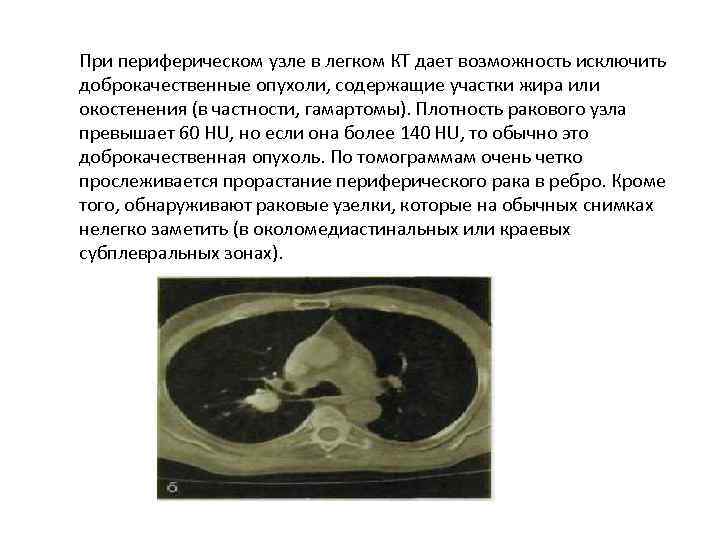

При периферическом узле в легком КТ дает возможность исключить доброкачественные опухоли, содержащие участки жира или окостенения (в частности, гамартомы). Плотность ракового узла превышает 60 HU, но если она более 140 HU, то обычно это доброкачественная опухоль. По томограммам очень четко прослеживается прорастание периферического рака в ребро. Кроме того, обнаруживают раковые узелки, которые на обычных снимках нелегко заметить (в околомедиастинальных или краевых субплевральных зонах).

При периферическом узле в легком КТ дает возможность исключить доброкачественные опухоли, содержащие участки жира или окостенения (в частности, гамартомы). Плотность ракового узла превышает 60 HU, но если она более 140 HU, то обычно это доброкачественная опухоль. По томограммам очень четко прослеживается прорастание периферического рака в ребро. Кроме того, обнаруживают раковые узелки, которые на обычных снимках нелегко заметить (в околомедиастинальных или краевых субплевральных зонах).